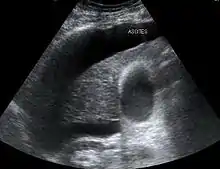

The use of ultrasound has become the standard of care when preparing a patient for paracentesis. Confirmation of an ascitic effusion reduces the risks associated with a dry or blind tap of the abdomen. Anatomic landmarks, such as the midline linea alba (abdomen) approach, were traditionally used as reference points for needle insertion. Phased array or curvilinear ultrasound transducers are typically used in the hospital and outpatient setting to identify ascites in the abdominal cavity. Fluid within the abdominal cavity appears hypoechoic or anechoic (black) on ultrasound. Morisons pouch (hepatorenal recess) is a common starting location in concordance with ultrasound FAST (Focused assessment with sonography for trauma) exam. Fluid collection can occur in a number of different locations and may be difficult to find, especially if the patient only exhibits a small volume of ascites. Measurement of the amount of fluid within the abdominal cavity is not necessary or very successful. Identification of sufficient fluid within the abdominal cavity for fluid analysis or to achieve a therapeutic benefit is all that is required to proceed to paracentesis. Ultrasound guidance of the paracentesis can also be used as an additional safety measure to ensure the needle stays within the ascitic fluid and avoidance of important vessels within the abdominal cavity. [5]